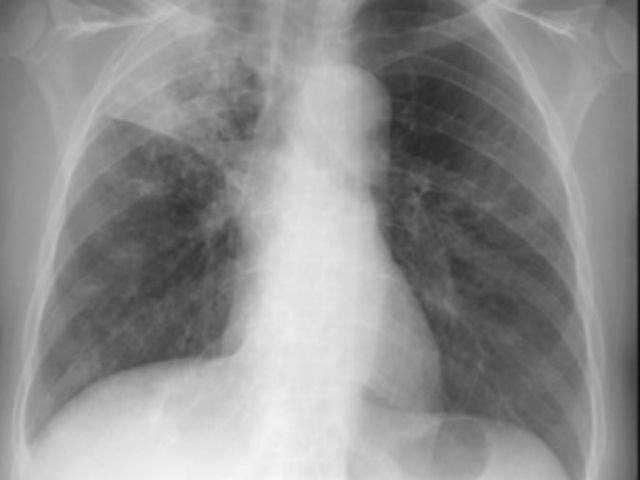

E’ stato il tema di grande attualita’ del prestigioso corso di formazione che si e’ tenuto a Lamezia Terme, nell’aula formazione dell’ospedale ”Giovanni Paolo II”, al quale hanno partecipato medici specialisti, veterinari, infermieri, biologi e tecnici di laboratorio biomedico, provenienti da tutta la regione. L’iniziativa ha assunto grande rilevanza non solo perche’ per la prima volta diverse figure professionali, impegnate quotidianamente nella gestione dell’infezione tubercolare, si sono riunite per affrontare le diverse problematiche sul tema, ma anche per l’autorevolezza dei relatori. La malattia tubercolare rappresenta ancora oggi una emergenza sanitaria mondiale. In Italia il numero di nuovi casi di malattia e’ intorno a 7 per 100.000 abitanti ed il rischio di contrarre la malattia e’ maggiore in determinati gruppi: immigrati, operatori sanitari, tossicodipendenti, immunodepressi, detenuti, anziani. Gli immigrati, che provengono da Aree geografiche ad alta endemia, spesso sviluppano la malattia nel Paese ospite, a causa delle disagiate condizioni igienico-sanitarie ed economiche in cui vivono. La strategia che l’ O.M.S. ha messo in atto per combattere il diffondere della malattia e’ basata principalmente sulla individuazione dei malati, dei portatori di infezione latente e sulla tempestiva identificazione dei ceppi di micobatteri multi-resistenti (MDR) ed estensivamente resistenti (XDR).